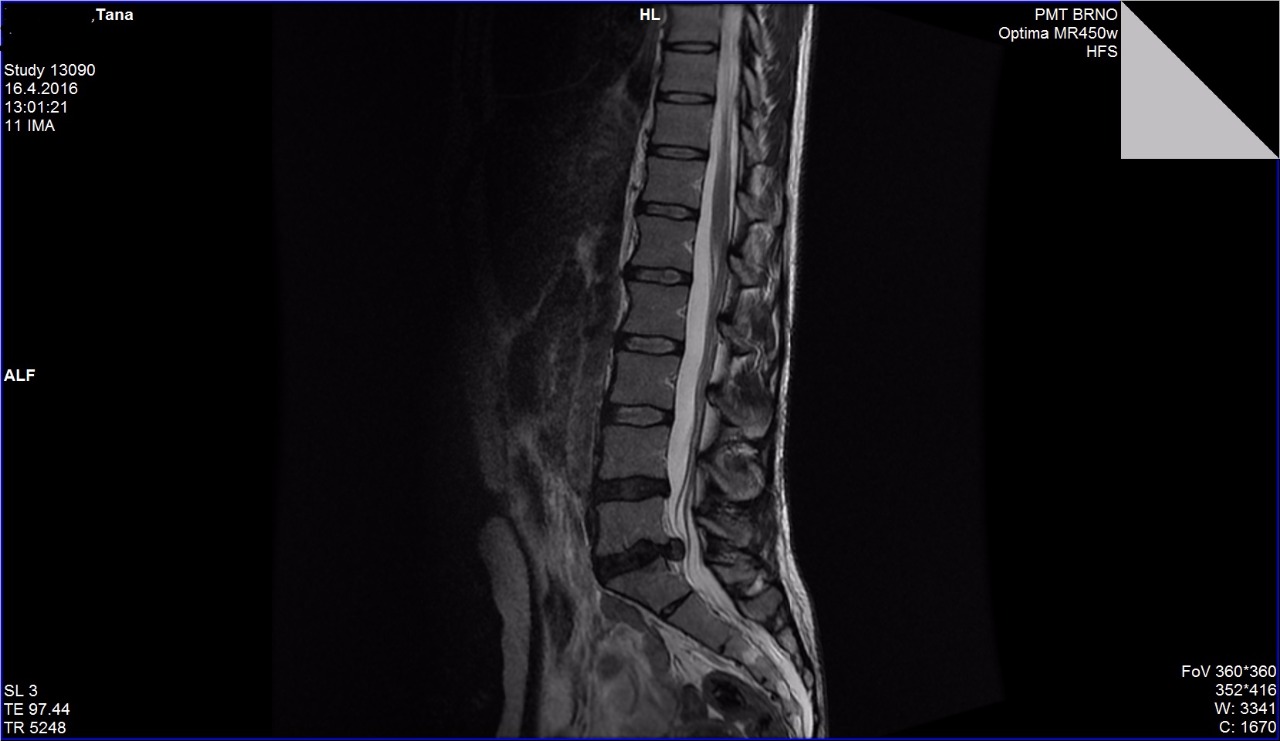

Po roce terapie - zlepšení o 4 mm

Byli jsme u Vás v srpnu a prosinci 2016. Od srpna 2016 cvičíme. Podle zprávy se plotýnka vrátila o 4 mm - z 10 na 6 mm, což je paráda. Celkově se cítím dobře a mnohem lépe než před rokem. Takže Vám strašně moc děkuju. Teď v poslední době se symptomy trošku zhoršily bych řekla, víc cítím občasný tlak na nerv, ale začala jsem pravidelně 2 krát týdně běhat, bylo trochu stresu, do toho jsem docela tahala těžký věci, takže bych to shrnula tak, že musím najet zase trošku opatrnější režim a ve cvičení samozřejmě nadále pokračovat (cvičíme jednou týdně).